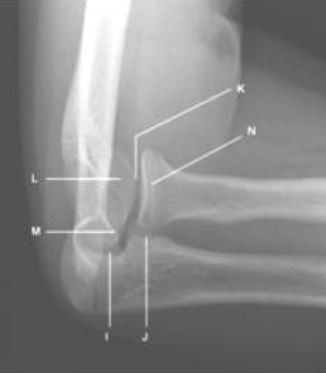

※현상 후 routine 모습

L : capitellum

K : HumeroRadial joint

N : Radial head

M : medial trochlea

I : humeroulnar joint

J:  radioulnar joint